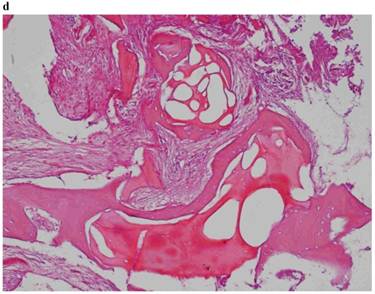

3) “Late” protocol

In this protocol, we can observe in the “test-side” “the presence of trabeculae of mature lamellar bone in a relaxed and richly vascularized stroma.” (Fig. 3)

Fig 3

Histological picture referring to “LATE Protocol”.